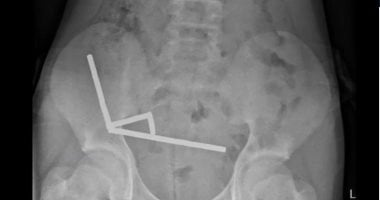

أظهرت الأشعة أن المغناطيسات تشكلت في أربع خطوط مستقيمة داخل أمعاء الطفل، وأن قوى الجذب أدت إلى نخر في أربع مناطق من الأمعاء الدقيقة والأعور، فجرى إجراء جراحة لإزالة الأنسجة الميتة واستعادة المغناطيسات.